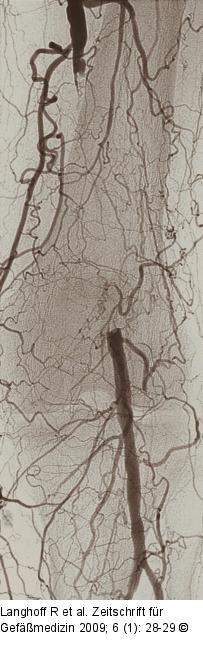

Abbildung 1: Arteria poplitea Verschluss der Arteria poplitea Rutherford Stadium IV |

Abbildung 1: Arteria poplitea

Verschluss der Arteria poplitea Rutherford Stadium IV |